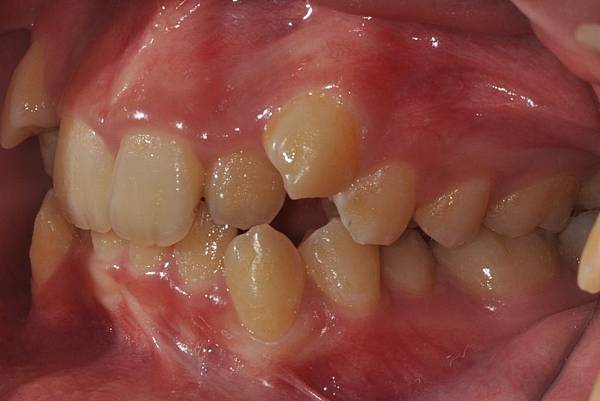

拔牙改善高位虎牙

虎牙妹的女神蛻變之旅~

此案例因為空間不足排列牙齒,

考量到不拔牙將使得牙齒前凸破壞患者原本和諧的側臉。

故上下左右各拔一小臼齒。